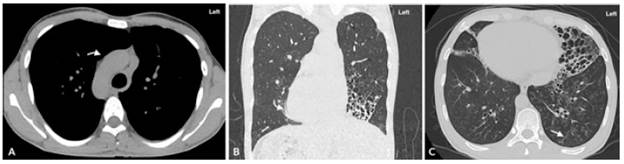

Symptomatology was interpreted as an infectious picture of low respiratory tract origin and possible bacterial sinusitis, for which antibiotic management was initiated with ampicillin sulbactam. Further paraclinical tests included a chest x-ray that showed dextrocardia, with no signs of consolidation or pleural effusion. This was complemented with high-resolution computed tomography (HRCT) (Figures 1 and 2) and a computed tomography (CT) of the paranasal sinuses (Figure 3).

After finding dextrocardia, it was necessary to ascertain visceral situs (normal, inverted, ambiguous). A simple tomography documented pulmonary bronchiectasis, as well as liver on the left side (Figure 4), leading to suspect KS; this was confirmed with findings of chronic sinusitis in paranasal sinus tomography. In addition, HRCT showed tomographic signs of infectious bronchiolitis.

Imaging plays a key role in proving the anatomical findings that support KS. However, the diagnostic precision of PKD is achieved with the elements mentioned above, all of which are difficult to access. Inadequate sweeping of pulmonary secretions causes bronchial dilatations or bronchiectasis that are observed as tubular opacities or ovoids of variable sizes in chest x-ray, a less sensitive method for its detection with respect to HRCT. 12

On the other hand, thin-section chest CT is the gold standard to detect bronchiectasis, although thick-section CT can also be used. The bronchial artery index is used to identify it and should normally be close to 1; however, it may increase during vasoconstriction or be normal during pulmonary hypertension. Therefore, the cardinal sign of bronchiectasis on a CT scan is the observation of bronchioles less than 1 cm from the pleural silhouette (Table 2). 12

According to the classification proposed by Reid 15, bronchiectasis is divided into cystic, cylindrical and varicose. Its characterization, in the case of this patient, was carried out by means of a CT scan that showed a predominantly cystic pattern. According to another case report 16, the three types of bronchiectasis have been described in patients with KS in equal proportions.